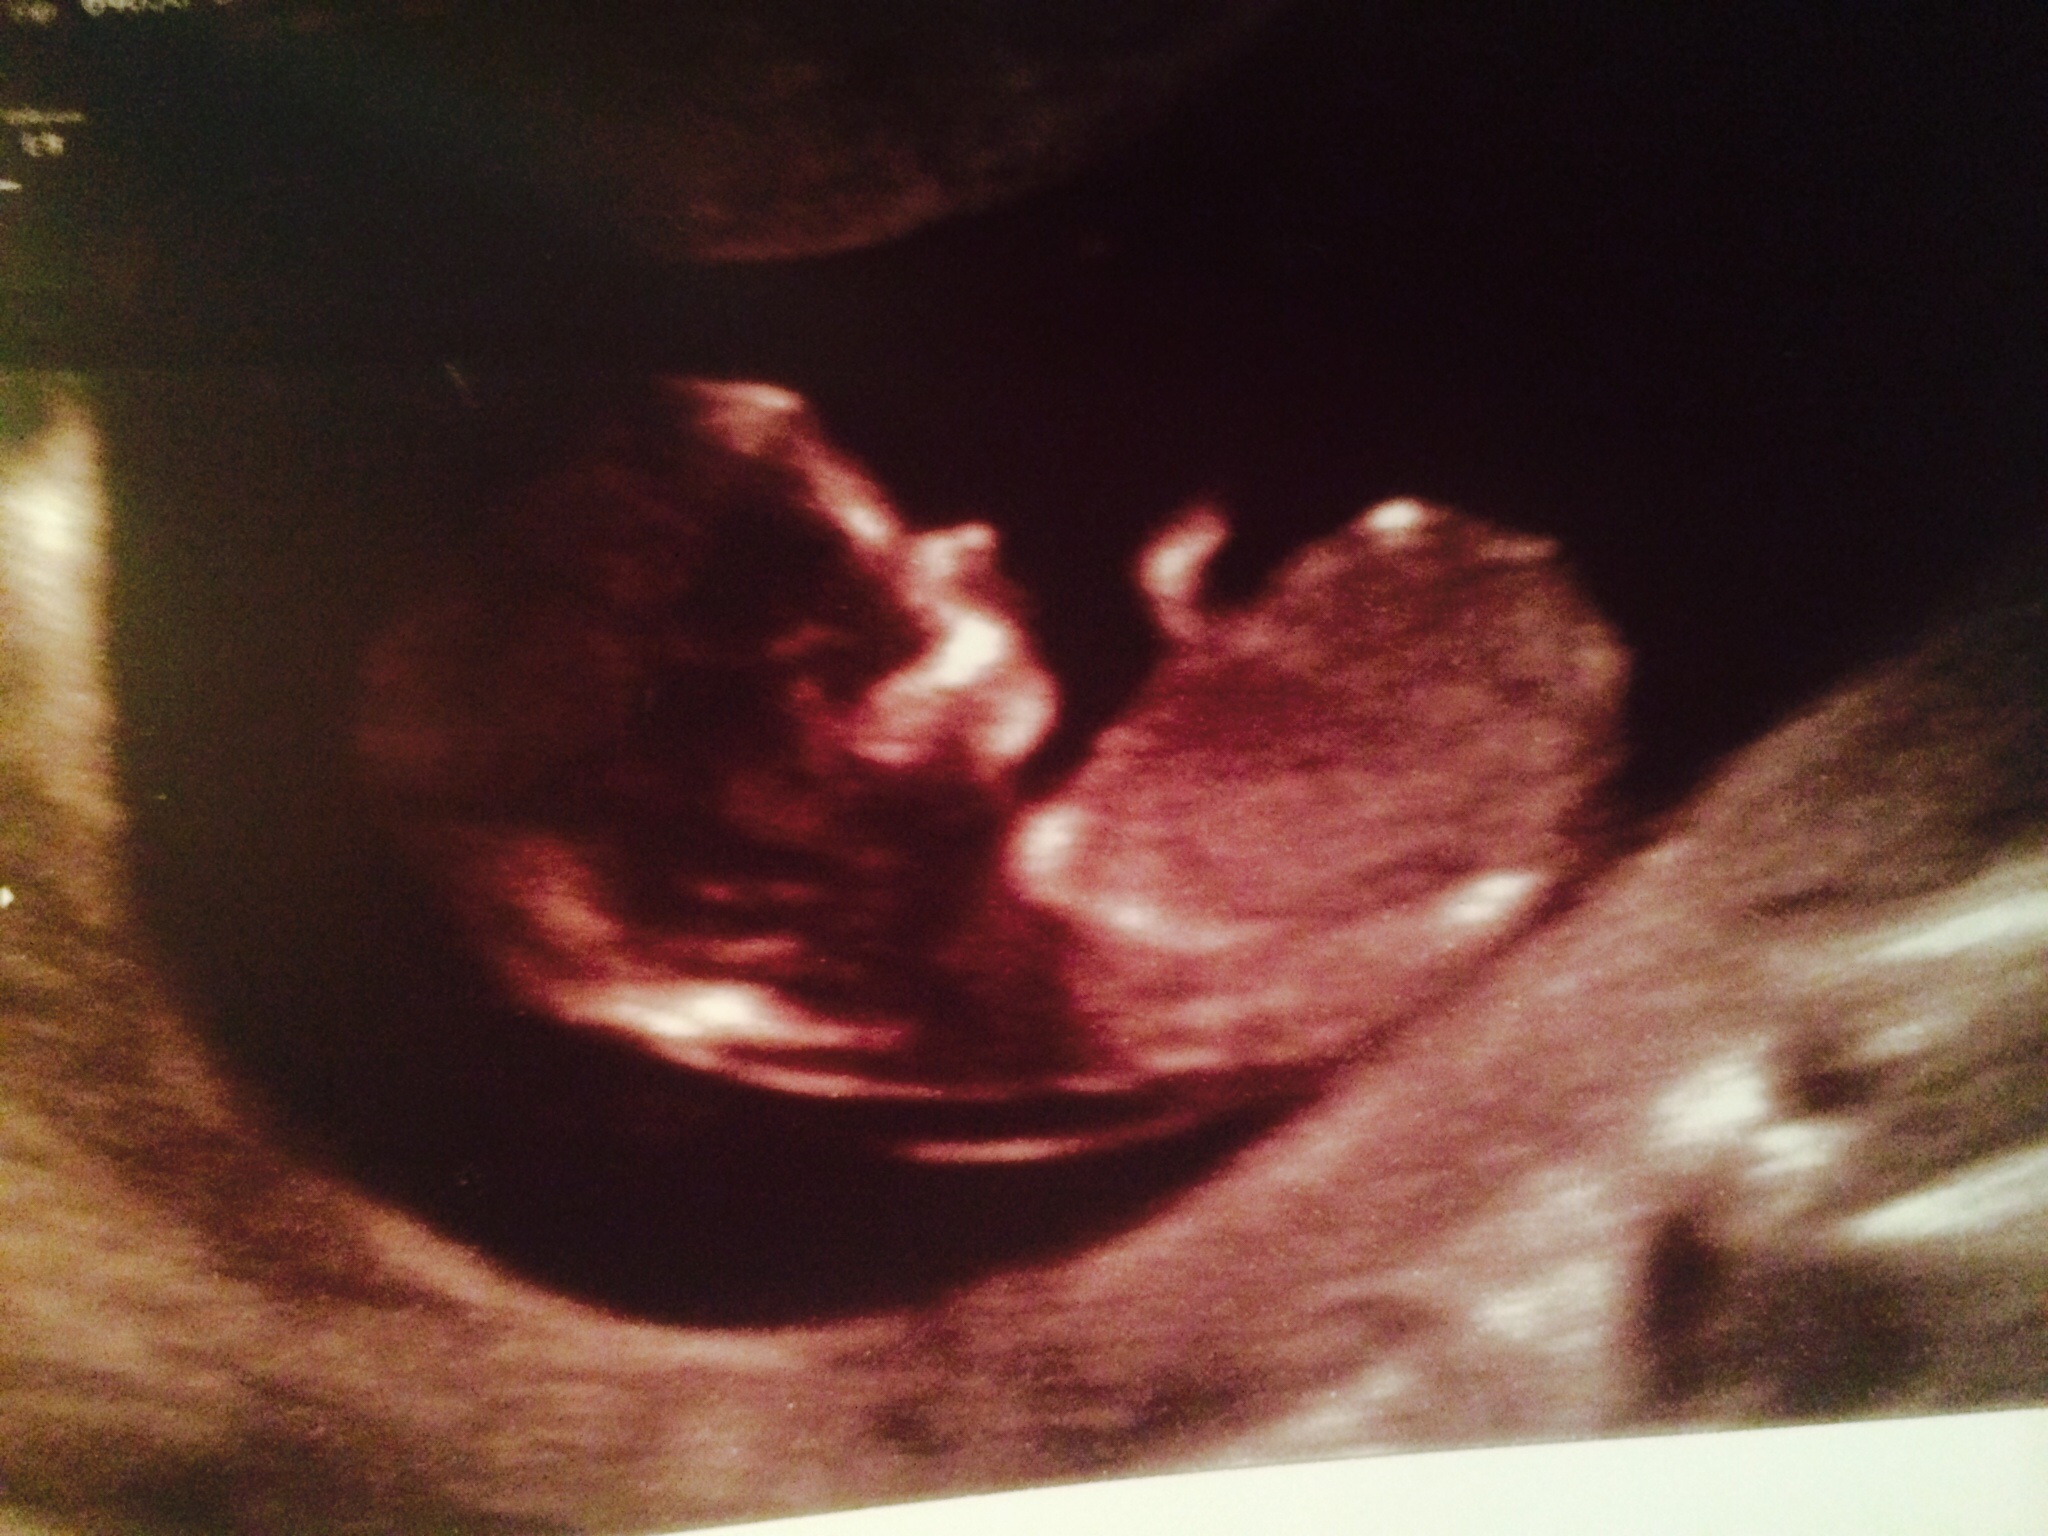

This is a 12w 1 day photo... Measured 12w 5d... Please help me identify the nub and guess. Thank you in advance :) Attachment 25561

Looks more girly to me, but I wouldn't say I'm sure of it

Difficult to say. If it were 12+1 I would have a boy lean, if it is 12+5 I would have a girl lean. More pics?

Can't quite put my finger on why, but looks boyish to me...

Looks a bit like my boys, good luck xx

I'd say girl

First pic I'm not seeing a nub but the first of the new pictures possibly a girl nub but looks like a very slight rise - that said if baby is 12+1 there is still time for the nub to rise so based on what we see you couldn't rule out a boy.

1st pic had me thinking boy, 2nd girl, sorry 50/50 on this one :( GL with blue :)